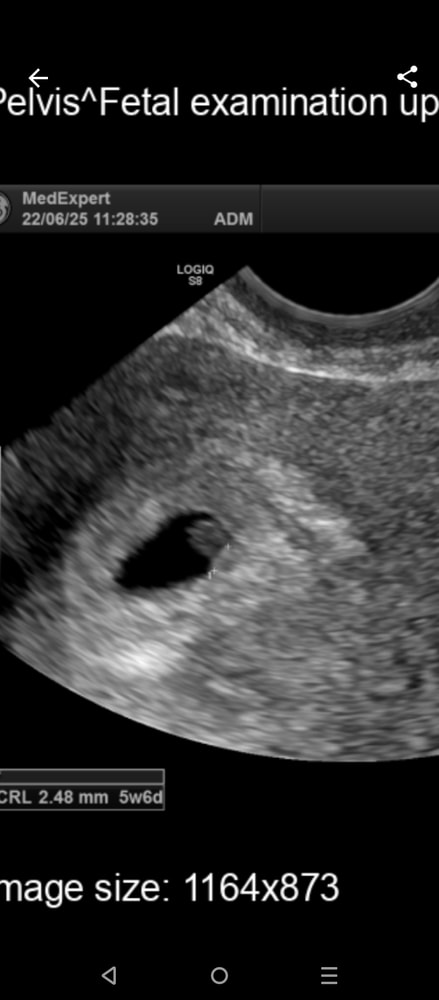

Сегодня сделала узи, вот что по узи

Плодное яйцо в матке сдв 5,6мм

Желточный мешок сдв 3,2 мм

Ктр эмбриона 2мм

Сердцебиения нет.

По узи срок 4недели.

Что-то мне не нравится маленькое плодное яйцо и большой для него желточный мешок. Опять же срок отстает очень прилично.